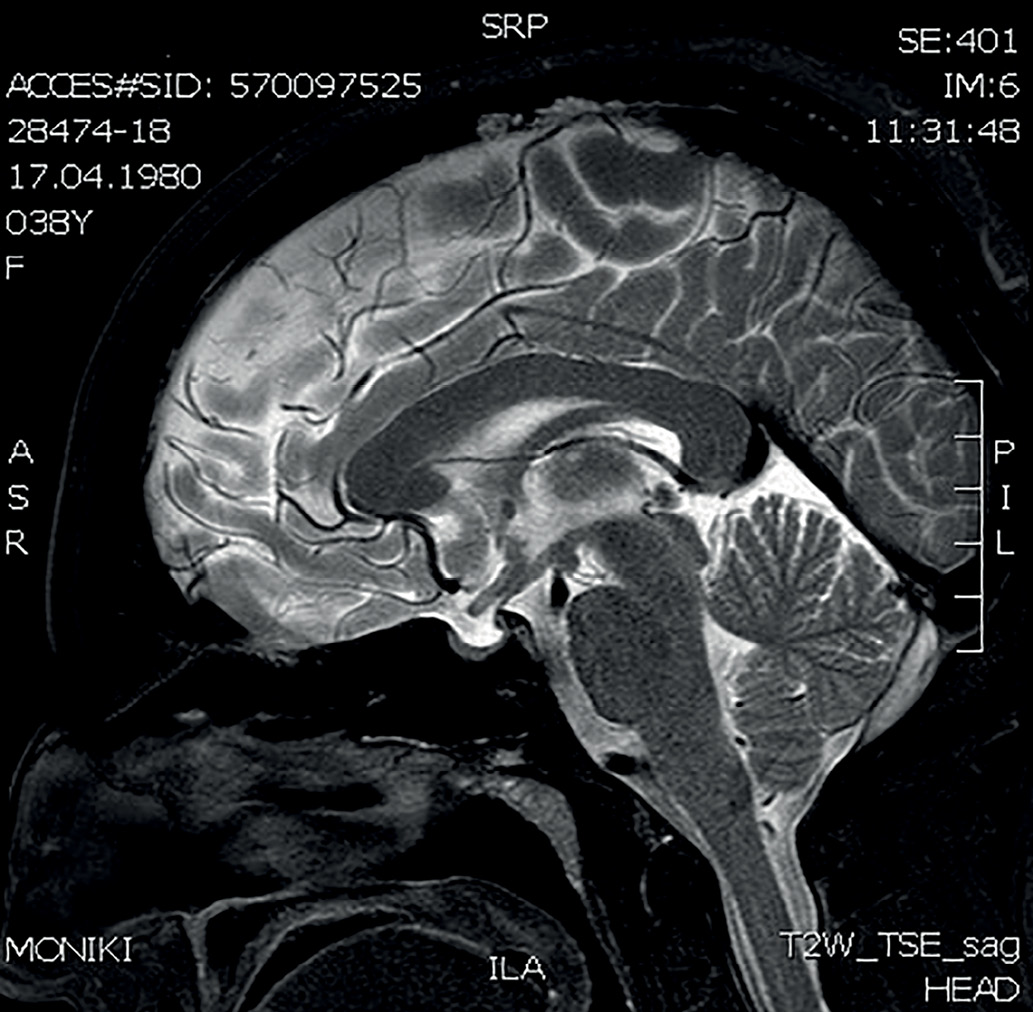

В 36 лет (в 2016 г.) стали беспокоить кашель, одышка. При проведении флюорографии органов грудной клетки выявлены очаговые образования в легких. Диагноз туберкулеза был исключен. Пациент был консультирован пульмонологом. При активном расспросе выяснилось, что с 2008 г. пациент отмечал появление на коже бугорков фиолетового цвета, которые появлялись преимущественно при длительном пребывании на солнце, затем спонтанно регрессировали, пациент не обращал наних внимания и никогда не указывал при обращении к врачу. При КТ органов грудной клетки (рис. 3–5) в легочной паренхиме выявлены множественные мелкие очаги перилимфатического распределения, а также лимфаденопатия средостения. Данные изменения с учетом клинико-лабораторной картины заболевания не противоречили диагнозу «саркоидоз с поражением легких, внутригрудных лимфоузлов, кожи, гипоталамо-гипофизарной области». От проведения морфологической верификации диагноза пациент отказался, однако особенности течения заболевания позволили исключить альтернативные причины изменений на КТ и определили показания к противовоспалительной и иммуносупрессивной терапии. Была начата терапия метилпреднизолоном в дозе 24 мг в сутки и метотрексатом 5 мг 1 раз в неделю, которую пациент принимал в течение 6 мес. Затем доза метилпреднизолона была снижена до 8 мг в сутки. На фоне проводимого лечения состояние пациента улучшилось, по данным МРТ головного мозга в динамике (от 24.11.2017) ранее выявленное образование в гипоталамо-гипофизарной области не определялось, МР-картина «пустого» турецкого седла (рис. 2). В связи с выраженной слабостью на фоне основного заболевания пациент самостоятельно отменил препараты левотироксина натрия, тестостерона, десмопрессина и каберголина, продолжая только прием метилпреднизолона. Слабость усилилась, увеличилось потребление жидкости до 5 л в сутки. При очередном гормональном обследовании отмечалось отсутствие компенсации, было подтверждено наличие пангипопитуитаризма и центрального несахарного диабета, т.е. нейроэндокринные нарушения носили необратимый характер (табл. 2).

Рисунок 2. МРТ головного мозга с к/у от 24.11.2017г (3 Тл)

МР-картина «пустого» турецкого седла, ранее выявленное образование в гипоталамо-гипофизарной области не определяется.

Figure 2. MRI of the brain with an appointment dated November 24, 2017 (3 T)

MRI picture of an “empty” sella turcica, a previously identified formation in the hypothalamic-pituitary region is not detected.